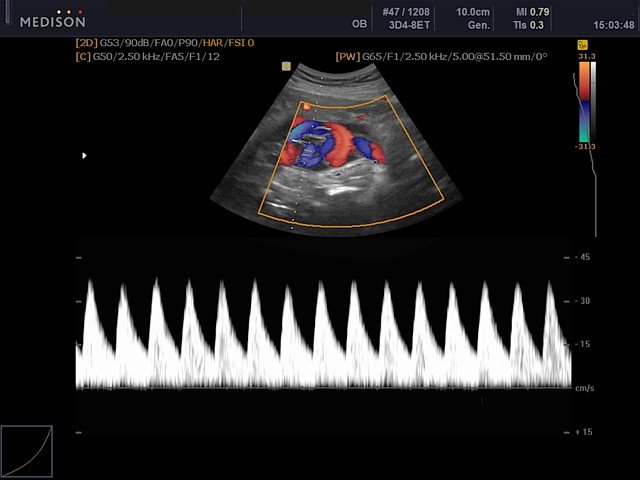

Пуповина, цветной допплер

Пуповина, CFM и PW